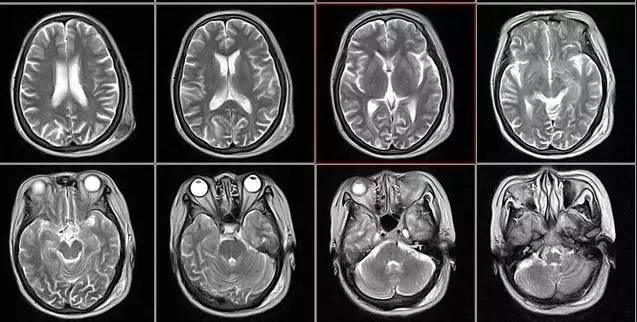

核磁共振:搖一搖再看

核磁共振機(jī)使用較強大的磁場,使人體中所有水分子磁場的磁力線方向一致,這時磁共振機(jī)的磁場突然消失,身體中水分子的磁力線方向,突然恢復(fù)到原來隨意排列的狀態(tài)。簡單說就相當(dāng)于用手搖一搖,讓水分子振動起來,再平靜下來,感受一下里面的振動。所以,核磁共振(MRI)也被戲說為是搖搖看的檢查。

2、頸椎腰椎——最佳選核磁、次選CT

頸椎病、腰椎間盤突出等椎間盤疾病需要觀察椎間盤與相應(yīng)的神經(jīng)根,要想更好觀察這些軟組織,最優(yōu)選擇就是核磁。同樣,對于關(guān)節(jié)、肌肉、脂肪組織檢查,核磁也是首選。